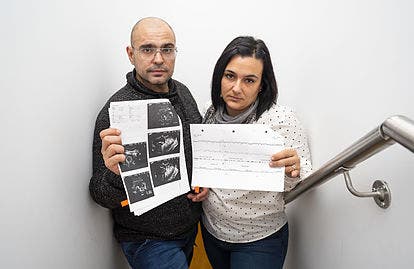

El Juzgado de Primera Instancia número 45 de Madrid condenó al asegurador del Hospital HM Nuevo Belén a pagarle el citado monto a la mujer que perdió a su hijo después que en el centro de salud decidieran retrasar el parto por cesárea de la madre a pesar del estado crítico del feto.

La juez consideró en la sentencia que el hospital desasistió a la mujer de 33 años en período de gestación desde el 28 de febrero de 2016. Impuso la indemnización a la compañía aseguradora W.R Berkeley España.

La resolución resalta que el acto de negligencia causó que la madre necesitara iniciar un tratamiento psiquiátrico, mientras que el padre que estuvo de baja laboral necesita tomar antidepresivos.

Los padres solicitaron en la demanda una indemnización de 179.407 euros por daños y perjuicios.